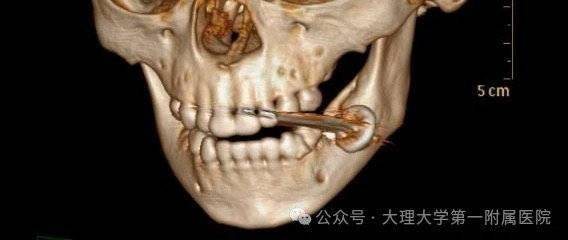

通過完善檢查,口腔頜面外科值班醫生發現電池的保護蓋和集電器卡在孩子的咬肌和頰肌之間。醫生稱,考慮到電池含有強堿性物質,一旦進入體內,會迅速釋放化學物質,對周圍組織造成嚴重的化學燒傷,甚至可能危及生命。另外,電池廢液中含有汞、鉛、鉻等多種重金屬,而汞是一種毒性很強的重金屬,對人體中樞神經破壞力很強。

口腔頜面外科值班醫生不敢有絲毫怠慢,立即聯系麻醉科安排急診手術,在孩子入院1小時內為他施行了“口腔爆炸傷清創術+異物取出術”。幸運的是,電池的爆炸傷局限在口腔軟組織多處穿孔,還沒將電池碎片吞下肚。

經過探查,將電池保護蓋、集電器及殘留碎屑完整取出,妥善止血,清理創口并對位縫合,快速解決了這個危機。目前,孩子無生命危險,在口腔頜面外科接受術后康復治療。